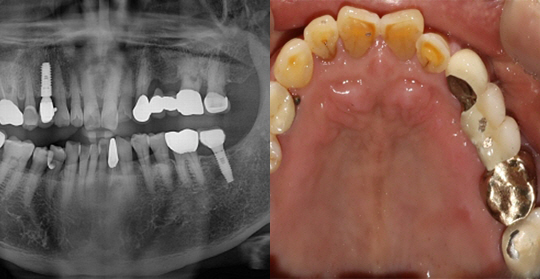

(61세 남 환자)